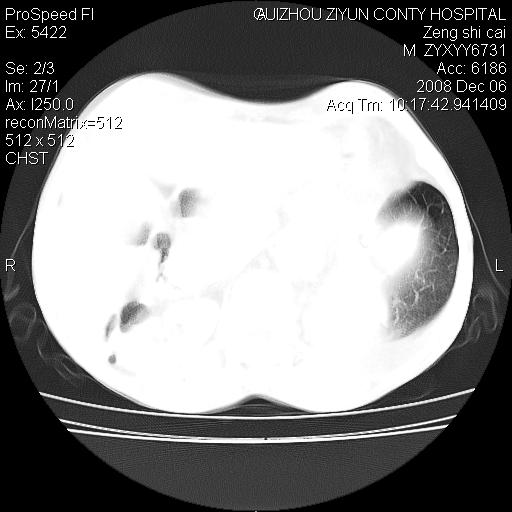

标题: CT16961:M、71岁,咳嗽半年,无血痰;胸片示右肺占位。 [打印本页]

标题: CT16961:M、71岁,咳嗽半年,无血痰;胸片示右肺占位。

右肺纵隔型肺癌伴纵隔淋巴结转移!双侧胸水!

1)考虑右肺上叶纵隔型肺癌伴纵隔淋巴结转移。2)心包积液,双侧胸腔积液。

右肺癌并纵隔淋巴转移,腹膜后转移可能性大,两侧胸腔积液

右肺上叶纵隔型肺癌伴纵隔淋巴结转移。心包积液,双侧胸腔积液。

右肺纵隔型肺癌伴纵隔淋巴结转移!双侧胸水\\心包积液

建议强化!主要鉴别是淋巴瘤与肺癌淋巴结转移。